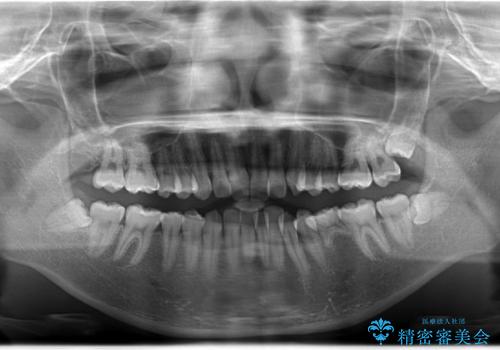

左下5番は先天性欠損のため乳歯は抜歯しインプラントにて欠損補綴しています。